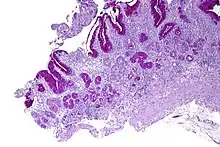

Micrograph showing nodular enterochromaffin-like cell hyperplasia, as demonstrated with chromogranin A immunostaining, in the body of the stomach. Parietal cells are not readily apparent. These changes are in keeping with autoimmune metaplastic atrophic gastritis, a histologic correlate of vitamin B12 deficiency anemia.

PA may be considered as an end stage of autoimmune atrophic gastritis, a disease characterised by stomach atrophy and the presence of antibodies to parietal cells and intrinsic factor.[36][37] Autoimmune atrophic gastritis, is localised to the body of the stomach, where parietal cells are located.[34] Antibodies to intrinsic factor and parietal cells cause the destruction of the oxyntic gastric mucosa, in which the parietal cells are located, leading to the subsequent loss of intrinsic factor synthesis. Without intrinsic factor, the ileum can no longer absorb the B12.[38] Atrophic gastritis is often a precursor to gastric cancer.[37]